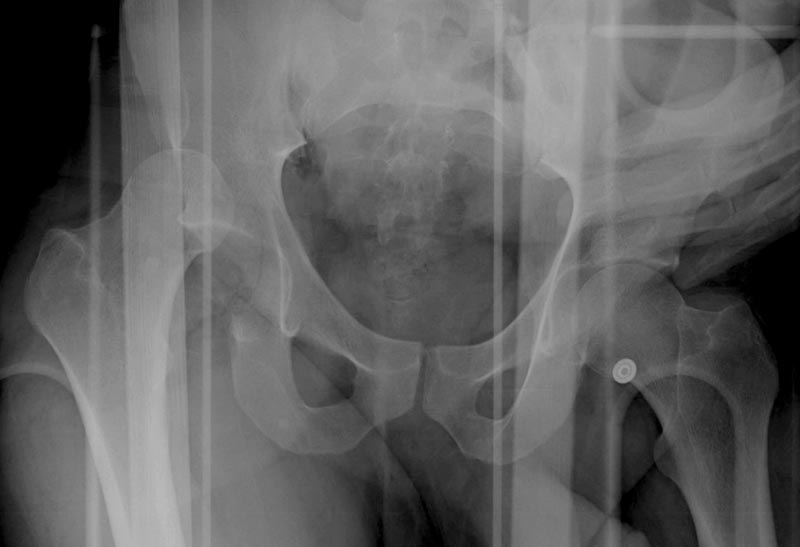

Выставлена на обсуждение (только одна проекция) рентгенограмма больного 25 лет, поступившего в приемное отделение, молодой дежурный врач сомневается в тактике лечения и спрашивает совета.

С его слов, больной стабилен,травму получил в результате автоаварии.Подскажите, что делать?Джолдас Кульджанов

5:24 Рентгенограмма таза, вызывают врача ортопеда (снимок N1), его диагноз: закрытый переломо-вывих правого тазабедренного сустава, получает добро на закрытую репозицию в приемном отделении